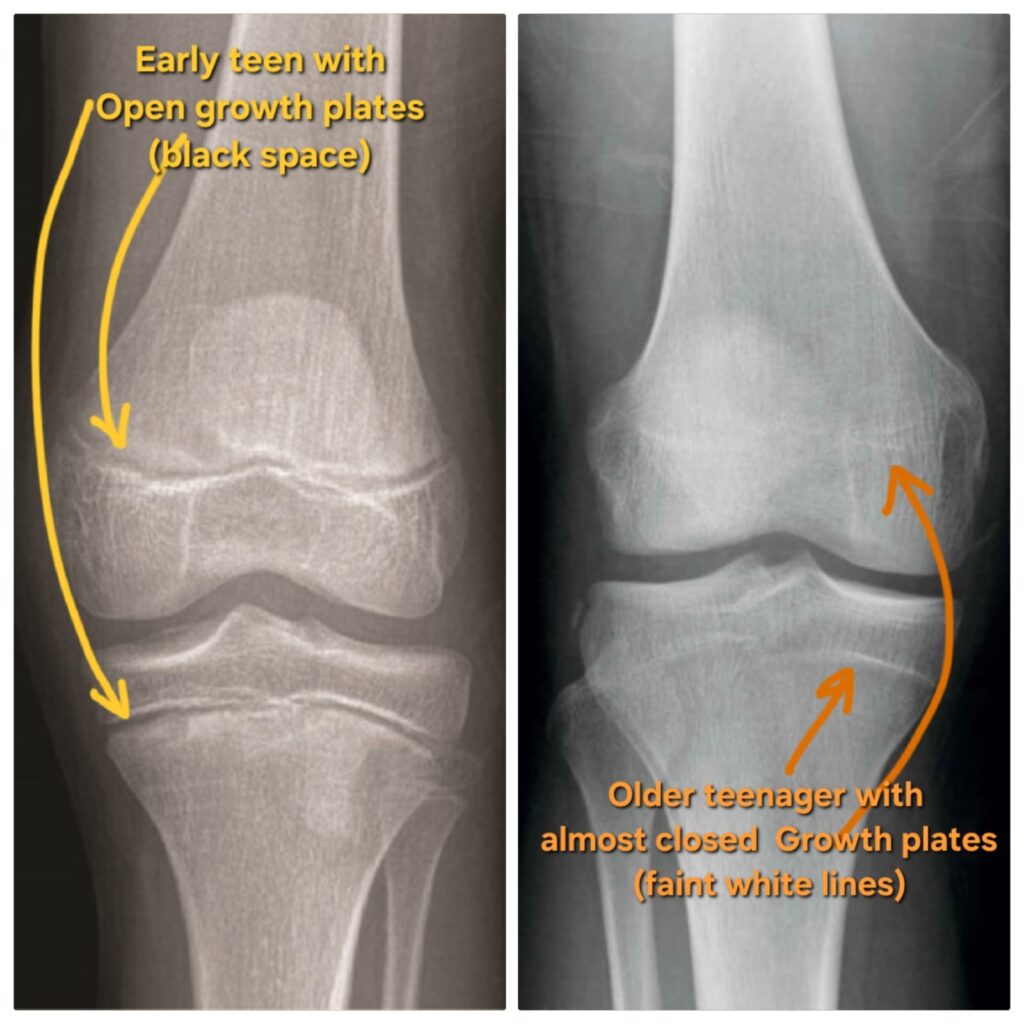

Children grow in height because of special areas at the ends of their bones called growth plates. As long as these growth plates are open, growth is possible. Once they close, height growth stops permanently.

A helpful way to picture this is to imagine a window that opens and then closes over time.

During childhood, the window is open and growth is slow and steady—like a light breeze.

With puberty, the breeze becomes stronger and growth speeds up.

As puberty progresses, the window slowly begins to close.

Once it closes fully, growth is no longer negotiable.